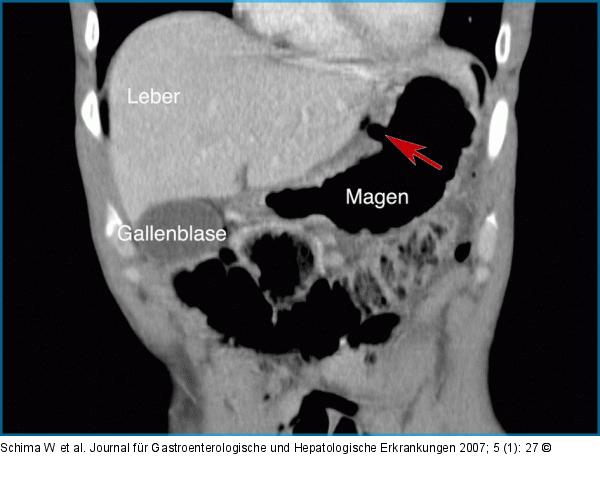

Abbildung 2: Ulkus Die 3D-Rekonstruktion des CT in parakoronaler Schnittführung zeigt die Lokalisation des Ulkus noch anschaulicher. |

Die 3D-Rekonstruktion des CT in parakoronaler Schnittführung zeigt die Lokalisation des Ulkus noch anschaulicher. |